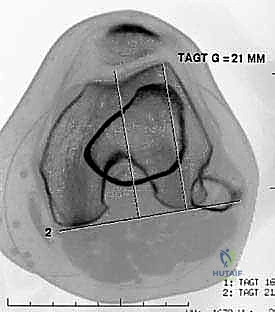

Advanced cross-sectional imaging, specifically MRI and occasionally CT, is indispensable. Axial CT or MRI is used to accurately measure the TT-TG offset, ensuring it falls within the acceptable range (< 15-20 mm) for an isolated MPFL procedure.

However, MRI is the primary modality for evaluating the soft-tissue envelope. We scrutinize the T2-weighted axial and coronal sequences to identify the exact location of the MPFL failure. We look for the classic "wavy" appearance of a detached ligament, surrounding edema, and the presence of a distinct stump at the patellar margin.

Crucially, the MRI must be reviewed for concomitant articular cartilage damage; osteochondral loose bodies originating from the medial patellar facet or the lateral femoral condyle are common and must be addressed concurrently.